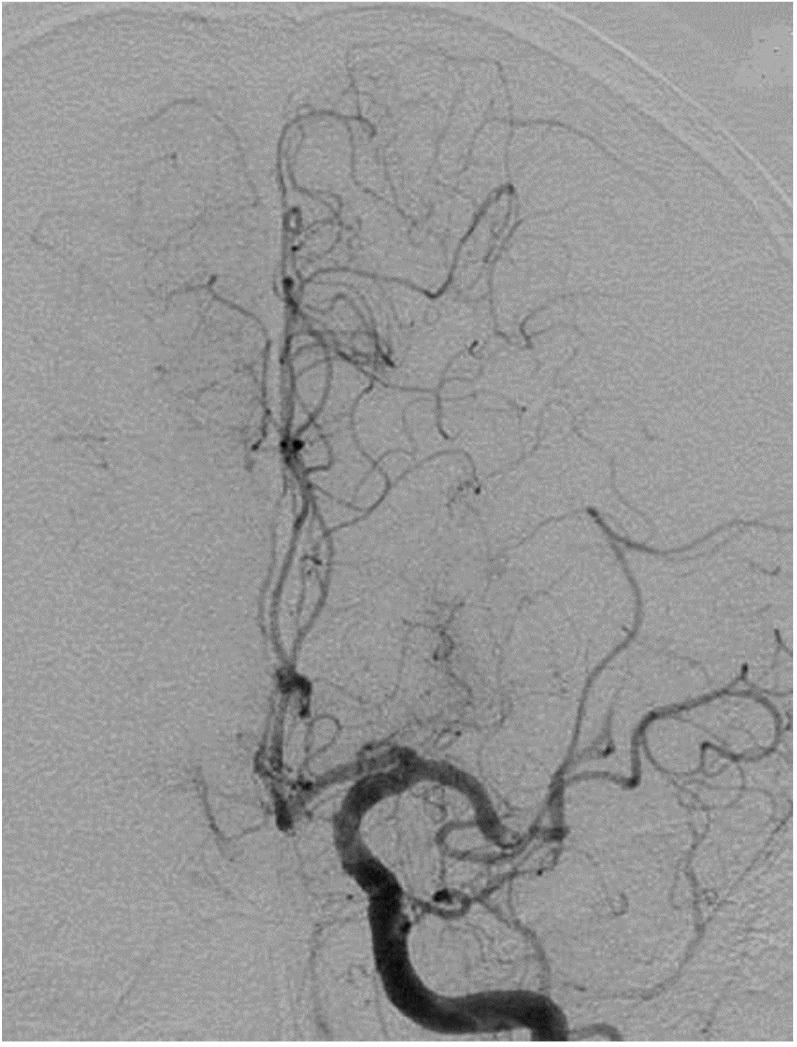

The optional endovascular approach for acute ischemic stroke is unclear. The Trevo stent retriever can be used as first-line treatment for fast mechanical recanalization. The authors developed a treatment protocol for acute ischemic stroke based on the assessment of clot quality during clot removal with the Trevo. This prospective single-center study included all patients admitted for acute ischemic stroke between July 2014 and February 2015, who underwent emergency endovascular treatment. According to the protocol, the Trevo was used for first-line treatment. Immediately after the Trevo was deployed, the stent delivery wire was pushed to open the stent by force (ACAPT technique). Clot quality was assessed on the basis of the perfusion status after deployment of the Trevo; continued occlusion or immediate reopening either reoccluded or maintained after the stent retriever had been in place for 5 min. If there was no obvious clot removal after the first pass with the Trevo, according to the quality of the clot, either a second pass was performed or another endovascular device was selected. Twelve consecutive patients with acute major cerebral artery occlusion were analyzed. Thrombolysis in cerebral infarction score 2b and 3 was achieved in 11 patients (91.7%) and 9 (75%) had a good clinical outcome after 90 days based on a modified Rankin scale score ≤ 2. Symptomatic intracranial hemorrhage occurred in 1 patient (8.3%). The overall mortality rate was 8.3%. Endovascular thrombectomy using the Trevo stent retriever for first-line treatment is feasible and effective.

急性缺血性卒中的选择性血管内治疗方法尚不清楚。Trevo支架取栓器可作为快速机械再通的一线治疗方法。作者基于使用Trevo取栓过程中对血栓质量的评估,制定了一种急性缺血性卒中的治疗方案。这项前瞻性单中心研究纳入了2014年7月至2015年2月期间因急性缺血性卒中入院并接受急诊血管内治疗的所有患者。根据该方案,Trevo被用作一线治疗。在部署Trevo后,立即用力推送支架输送钢丝以打开支架(ACAPT技术)。根据Trevo部署后的灌注状态评估血栓质量;持续闭塞或立即再通,在支架取栓器放置5分钟后要么再次闭塞要么保持通畅。如果使用Trevo首次取栓后没有明显的血栓清除,根据血栓质量,要么进行第二次取栓,要么选择另一种血管内装置。对连续12例急性大脑中动脉闭塞患者进行了分析。11例患者(91.7%)达到脑梗死溶栓评分2b和3分,90天后基于改良Rankin量表评分≤2,9例(75%)患者获得良好的临床结局。1例患者(8.3%)发生有症状性颅内出血。总死亡率为8.3%。使用Trevo支架取栓器进行一线治疗的血管内血栓切除术是可行且有效的。